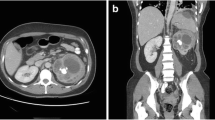

Focal XPN is a disease limited to a renal segment or one pole of a duplex system. US shows a localised hypoechoic mass, frequently without a stone obstructing the calyx (Fig. 1) [5, 12]. The kidney appears otherwise normal. CT demonstrates a well-defined localised intrarenal mass with water-like attenuation. There may also be a rim enhancement attributed to granulation tissue or compressed renal parenchyma. Perirenal extension may exist (Fig. 2). These findings are virtually impossible to differentiate from renal abscess (Fig. 3) or neoplasm (Fig. 4) [13, 14]. There are few data about MRI findings in the focal form. The lesion is isointense with the renal parenchyma on T1-weighted imaging and has slightly low signal intensity on T2-weighted. These findings suggest a fluid with a very high protein content. MRI, and especially the T2 sequences, are useful with the absence of hyperintensity in the differentiation of XPN from tumoural masses. The different signal intensity of the solid component of XPN on T1-weighted images, compared to the renal parenchyma, depends on the amount of xanthoma cells occurring in the lesion [1, 3, 15, 16].

Atypical diffuse XPN. a Transverse and b coronal reconstructions CT show an atrophied kidney with multiple lithiasis, dystrophic calcifications in low attenuation areas of parenchyma destruction (discontinuous arrows), perirenal extension (white arrows) and retroperitoneal adenopathies (black arrows)